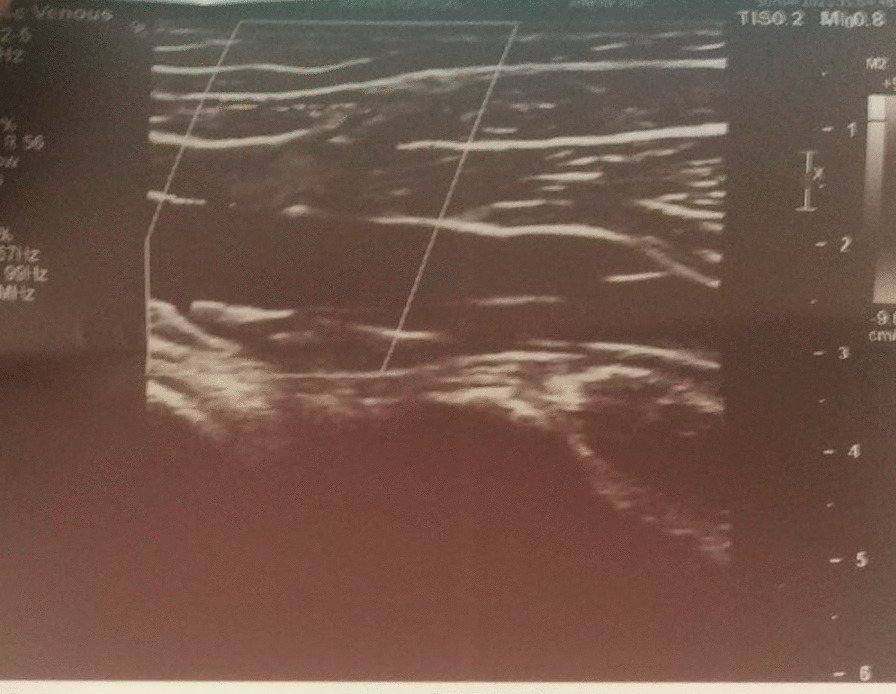

Fig. 1.

Doppler of proximal end of Superficial Saphenous Vein

Report of April 8, 2021.

Superficial Thrombophlebitis of SSV.

Details: Echogenic thrombus causing complete narrowing of proximal 1/3rd of SSV was noted, with almost similar findings in previous Doppler report. The thickening of the proximal part of SSV was 3.5 mm in diameter (Fig. 1) whereas that of the distal part of SSV was 2.4 mm in diameter (Fig. 2).